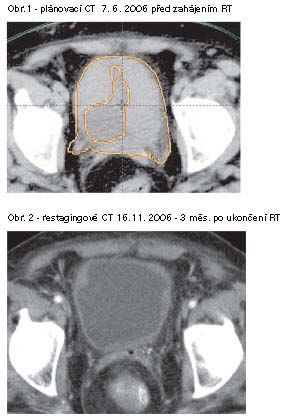

CT dokumentace efektu RT:

Pacientka 60 let, uroteliální karcinom G3, T4aN2M0, RT 66Gy v r.

2006, 3/2008 doba sledování 20 měsíců (PR blízká CR)